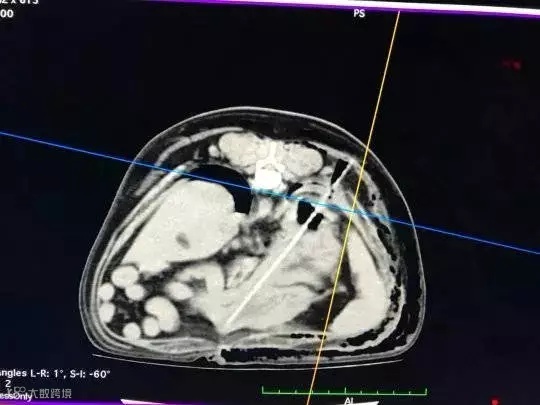

第二天,赶紧带它去了医院,看到CT之后才知道:Monty的胸腔,被一根细长的东西刺穿了它的横膈膜和肺部!

手术取出来一看,竟是一根烧烤竹签。

好在主人发现的及时,最后Monty才没有大碍。